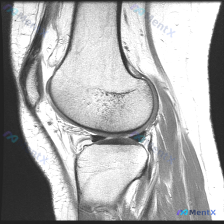

疑诊膝关节软骨异常?这份单幅T1矢状位MRI的判读思路值得捋捋

整理了一份很有参考意义的影像读片病例,核心问题是:这张膝关节MRI-T1序列矢状位图像上,能观察到软骨异常吗?把整个分析思路分享给大家。

这是一幅标准的膝关节矢状位T1加权像,图像对比度良好,骨髓腔呈正常高信号(脂肪髓),皮质骨呈低信号,解剖结构显示清晰,无明显运动或金属伪影;图像涵盖股骨远端、胫骨近端、髌骨、髌腱、股四头肌腱及部分髌下脂肪垫和关节间隙。

- 关节软骨:股骨髁关节面及胫骨平台关节面软骨呈中等信号,轮廓连续,未见明确的软骨全层缺损或剥脱

- 关节间隙:胫股关节间隙保持良好,无明显狭窄,髌股关节关系大致正常

- 韧带与肌腱:前交叉韧带为条索状低信号影,走行连续,无信号增高或中断;髌腱和股四头肌腱形态信号均无明显异常

- 半月板与关节内结构:半月板前后角呈典型三角形低信号,边缘锐利,内部无异常高信号,形态无移位;髌下脂肪垫信号均匀,无明显水肿;关节腔内无显著积液征象

针对问题「图像中是否可观察到软骨异常」,基于当前单幅图像的结论是:未见明确的软骨异常征象。影像分析显示股骨髁及胫骨平台关节面软骨轮廓连续,信号均匀,没有发现全层缺损或剥脱等异常表现。